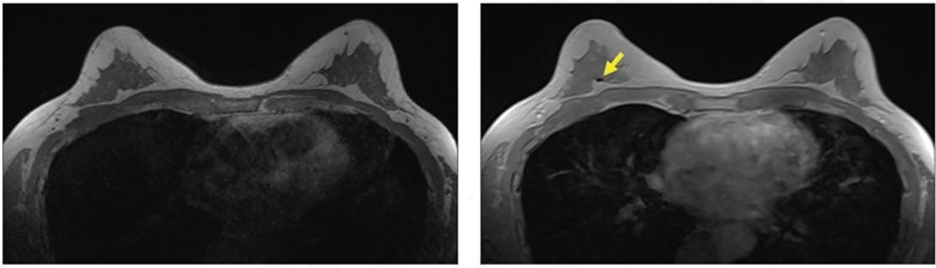

57-year-old patient with breast biopsy clips who underwent breast MRI for high-risk screening. A. Axial T1-weighted non-fat-saturated MR image shows no area of signal void. No reader detected clip using this sequence. B. Axial contrast-enhanced in-phase Dixon image shows signal void in right breast (arrow), which corresponded with MammoMark/CorMark Bread Tie biopsy clip. All three readers detected clip on this sequence, with confidence scores of 4, 3, and 2; assessments all classified as true positives (i.e., detected with confidence score ≥2).

“Compared with clinical sequences, contrast-enhanced in-phase Dixon had higher sensitivity for detecting breast biopsy clips on MRI, as well as higher reader confidence and contrast-to-noise ratio (CNR), without change in positive predictive value (PPV),” wrote corresponding and co-first author, Michael W. Taylor-Cho, MD, MPH, of Duke University Medical Center in Durham, NC.

Ultimately, compared with T1W NSF, STIR, and T1WFS sequences, the contrast-enhanced in-phase Dixon sequence evidenced the highest sensitivity for breast biopsy clip detection (85.1% vs. 26.6%-78.2%), highest reader confidence (3.5 vs. 1.7–3.0), and highest CNR (4.05 vs 0.54–1.21), without a significant difference in PPV (96.4% vs. 92.2%–96.1%).